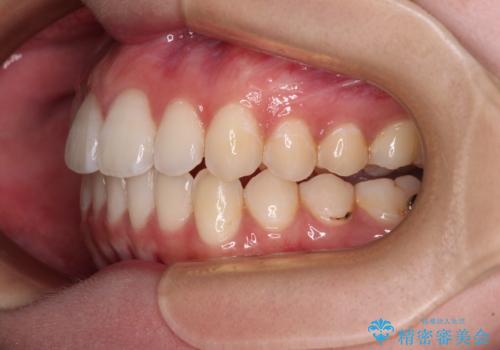

上下前歯の突出感とデコボコを気にして来院された患者様です。

インビザラインによる上下歯列の側方拡大と後方移動、必要に応じてIPR(歯と歯の間を削る)によりスペースの獲得により歯列を整えることとしました。

治療途中、出産や転居があり、2年ほど治療期間が長くなってしまいましたが、前歯の歯並びや飛び出した感覚を無事に改善させることができました。